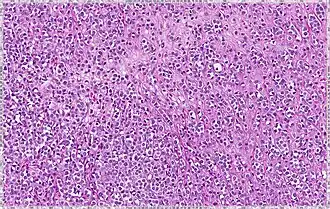

Type Prevalence Description Image

Solid 10% Sheets of classical-appearing cells with little intervening stroma

Alveolar 5% Aggregates of classical-appearing cells